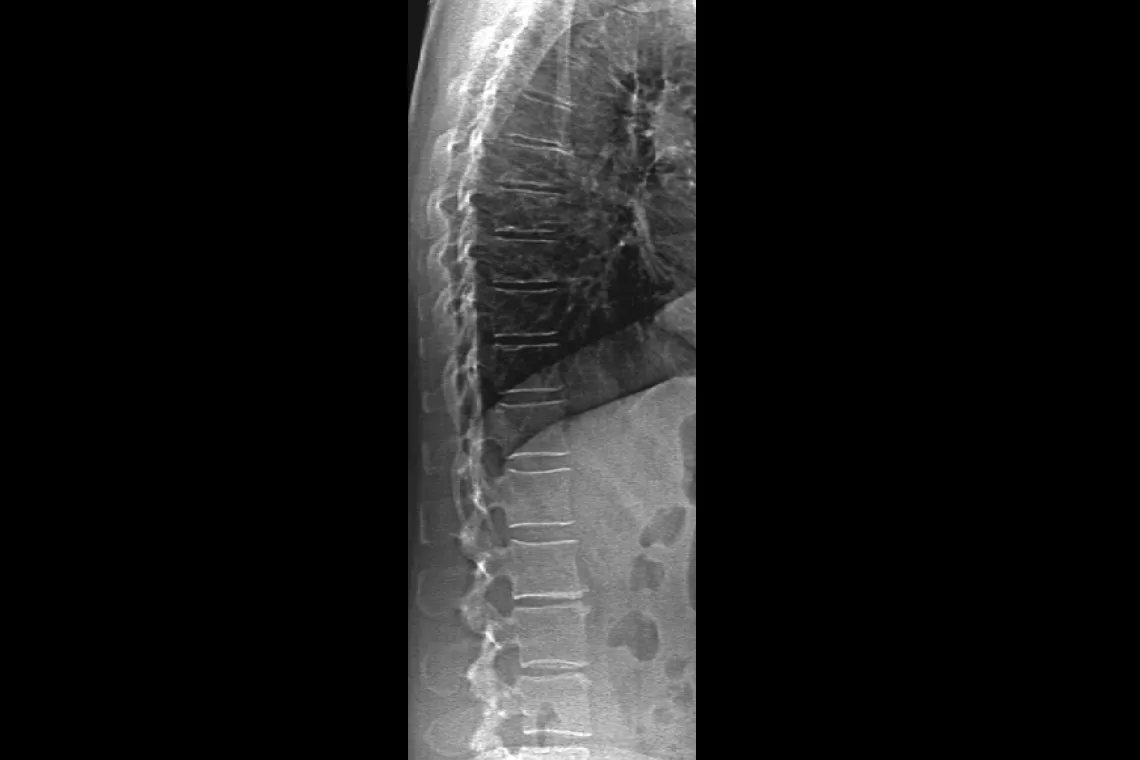

Horizon DXA produces radiographic quality images of the entire femur for assessment of potential atypical femur fractures.31 A quick, 15-second scan reveals cortical thickening of the bone, making it fast and easy to monitor the effects of bisphosphonate therapy over time.

Visualise calcified plaque in the abdominal aorta, which may be a significant indication of heart disease and stroke, two of the leading causes of death in men and women.

Assess fracture risk by combining an accurate measurement of bone density with high-resolution vertebral imaging. You can identify spine fractures with a low-dose, single-energy image in 10 seconds.

Improve accuracy and reduce post-exam analysis errors with precise, software-assisted placement of inter-vertebral disc spaces for graphic analysis.